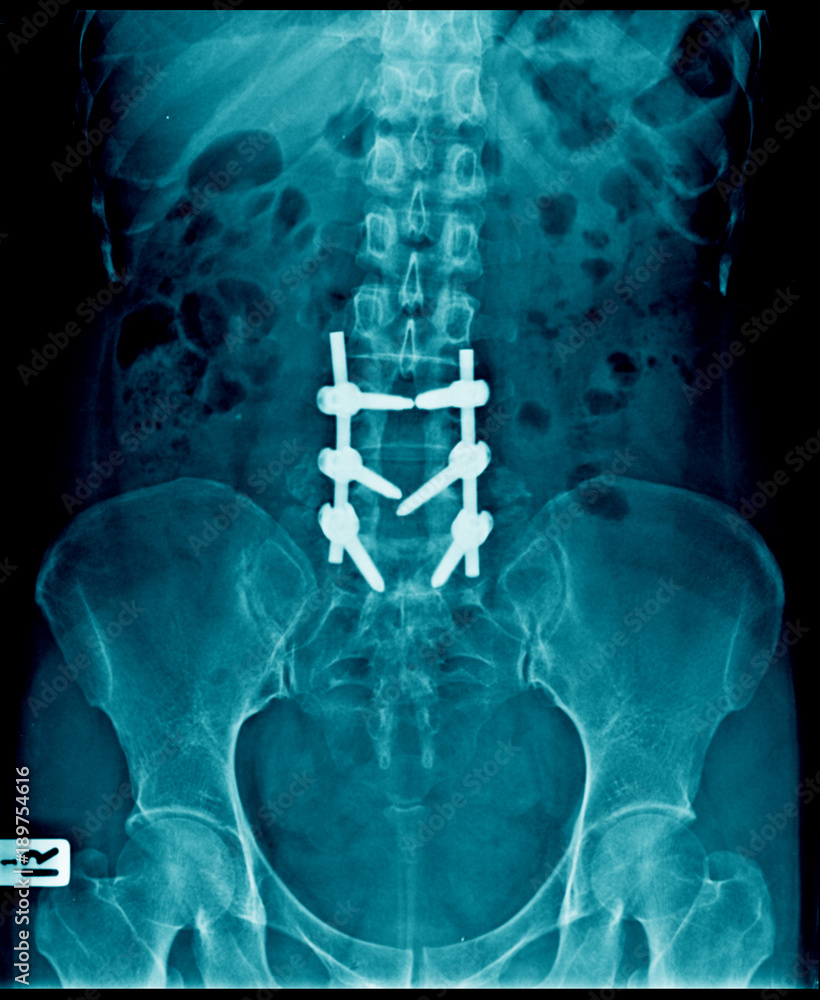

From stock.adobe.com

compression fracture and post operation to use internal fixation lumbar Compression Fracture Surgery Recovery Time Be sure to follow your provider’s instructions carefully so you can heal properly. Two common methods, vertebroplasty and kyphoplasty, generally have a faster recovery time because your surgeon. Vertebroplasty and kyphoplasty are minimally invasive procedures used to treat vertebral compression fractures of the spine. Procedures / kyphoplasty is a procedure to treat compression fractures, usually caused by osteoporosis or spinal. Compression Fracture Surgery Recovery Time.